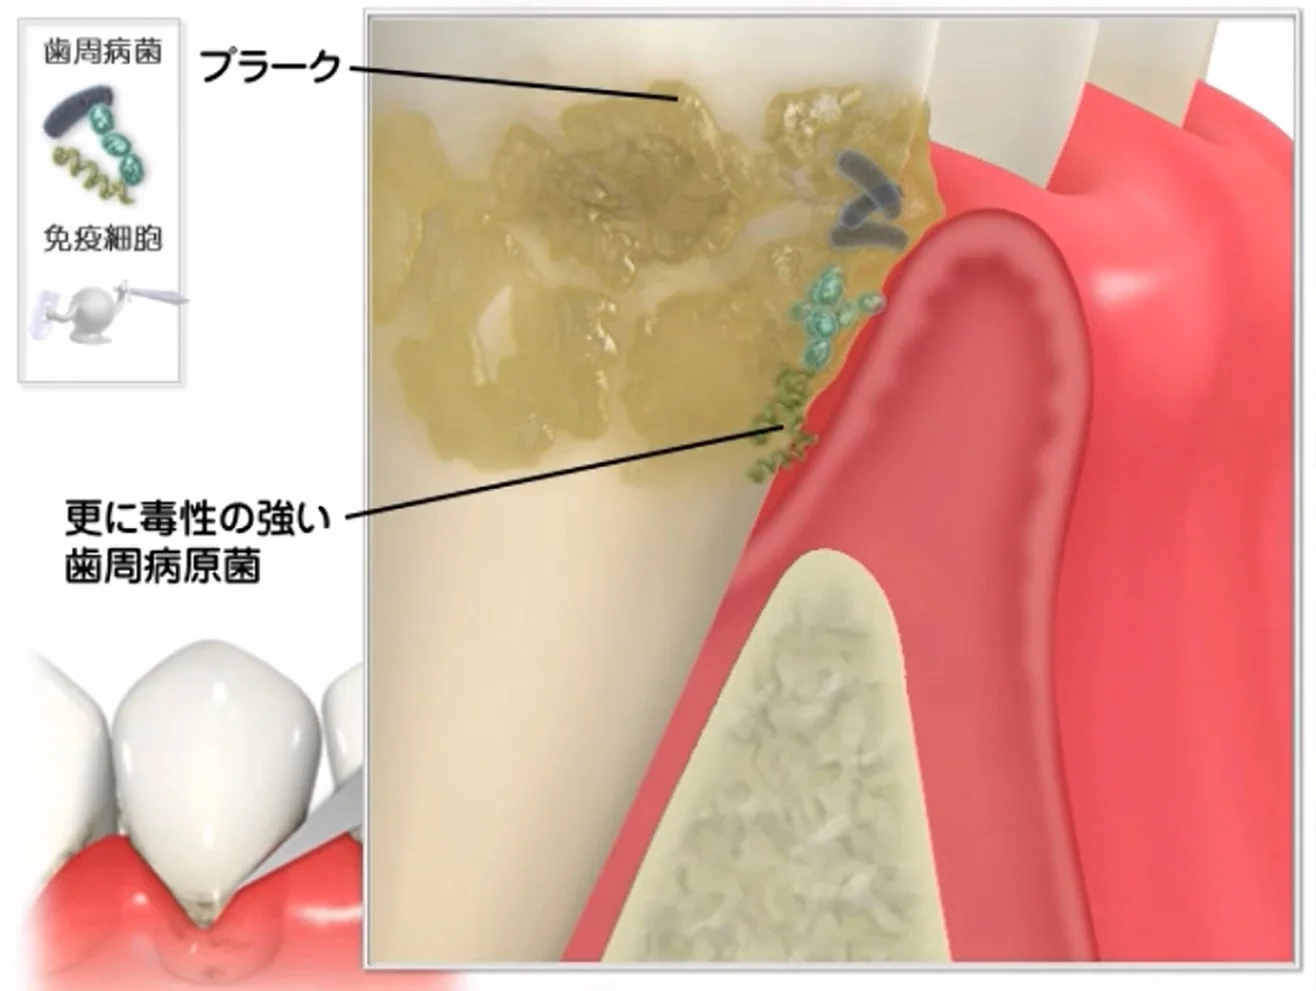

Q&A~歯周病ってなに?②~

こんにちは。 今回は前回に引き続き、歯周病について書いていきたいと思います。 思った以上のボリュームで、一気には書けませんでしたからね・・・(;'∀') 前回までのあらすじ ~プラークが付着し続けると、炎症が長引き歯肉の接着が外れて、歯周病…

Q&A~歯周病ってなに?①~

こんにちは。 今日はテレビや雑誌などでも耳にする機会の多い「歯周病」について書いていきたいと思います。 とはいえ、1回で書ききれるものではないので、そもそもの病態というか、その進み方を書いていきます。 ちなみに、進み方だけでも、すっごい長く…

続きを読む →